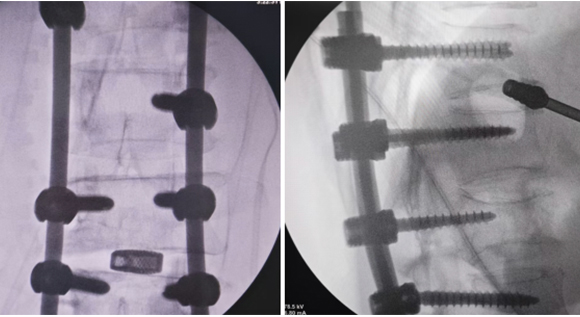

脊柱脊髓神经微创中心以微创技术为引领,以功能恢复为目标,主要治疗脊柱外伤、肿瘤、退行性病变、脊柱畸形等疾病。团队利用神经外科显微技术,结合神经内镜微创技术,对脊柱间盘变性疾病、颈腰椎管狭窄、颈腰椎间孔狭窄、颈腰椎间盘突出、颈腰椎体不稳、脊柱骨折、寰枢椎脱位、脊柱肿瘤、椎管内肿瘤、脊髓损伤、脊髓空洞、脊髓栓系等疾病进行高效、特色手术治疗,如颅颈交界区畸形寰枕减压内固定术、脊柱肿瘤全脊椎切除内固定术、微创椎管内肿瘤切除术、微创脊柱旁肿瘤切除术、寰枢椎脱位椎间融合内固定术、脊柱骨折微创经皮椎弓根钉内固定术、经椎间孔椎间融合内固定术(MIS—TLIF)等,最大程度降低脊柱脊髓手术创伤,具有创伤小、输血少、恢复快、口碑好,出院早等优势。